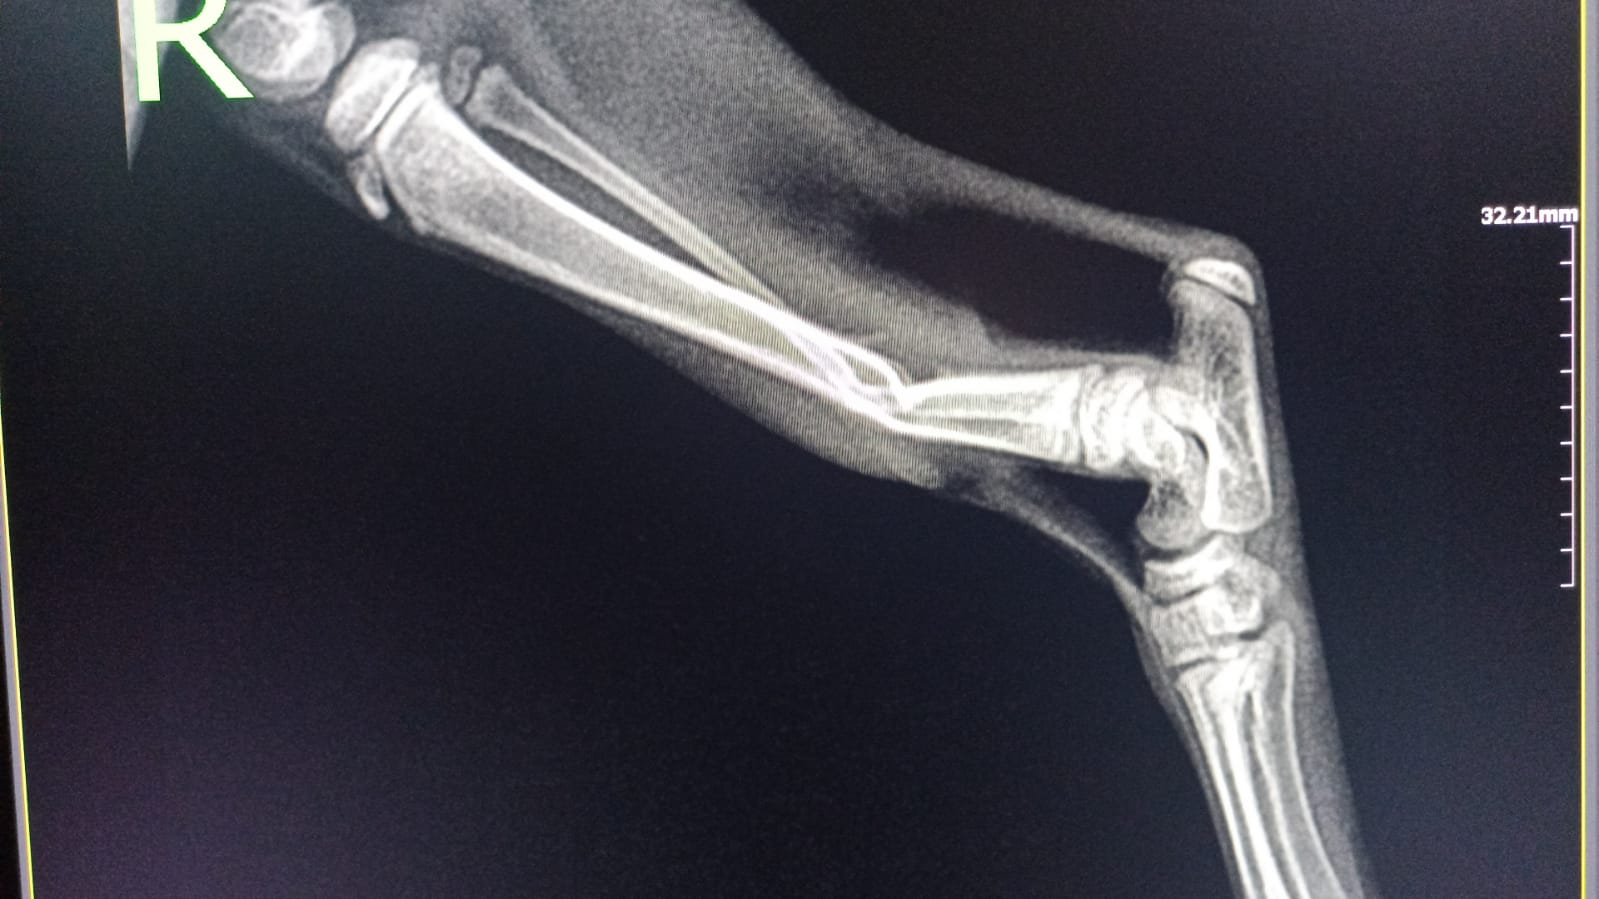

RTG wykazało złamanie w 1/3 dalszej kości strzałkowej oraz kości piszczelowej typu zielona gałązka.